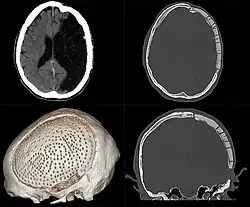

Frühere Verfahren benutzten eine Goldplatte oder Knochen-Transplantate, aktuell kommen Kunststoffe wie Polymethylmethacrylat (PMMA), Metalle wie Titan, verschiedene Keramiken oder bevorzugt körpereigener Knochen, oft der entnommene Knochendeckel bei einer Entlastungsoperation (Kraniektomie), zur Anwendung.[1]

Häufig wird ein der Kontur des Schädels individuell angepasstes Implantat benötigt. Dieses kann durch Laser-Sinter-Verfahren oder anderen 3D-Druckverfahren erzeugt werden.[2]